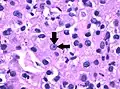

Светлоклеточный рак почки высокой (3-й) степени злокачественности. Окраска гематоксилином и эозином. Увеличение в 100 раз. Стрелочки указывают на чётко видимое ядрышко клетки.